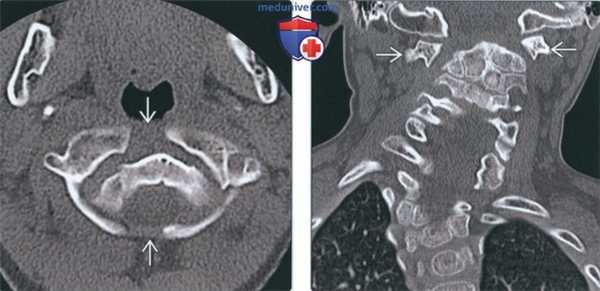

(Слева) На аксиальной КТ в костном окне определяется уменьшение передне-заднего размера на фоне его гипоплазии наряду с расщеплением и срединными дефектами передней и задней дуги. Определяется утолщение и дисплазия зубовидного отростка.

(Справа) На сагиттальной КТ в костном окне у пациента с расщеплением С1 определяется легкая дисплазия зубовидного отростка и патологическая гипоплазия С1 с тяжелым стенозом позвоночного канала. Обратите внимание на сопутствующее нарушение сегментации С2/С3.

(Слева) На аксиальной КТ в костном окне определяются большие срединные костные дефекты передней и задней дуги С1. Широкие щели свидетельствуют о нестабильности.

(Справа) На корональной КТ в костном окне на фоне врожденного сколиоза определяются распространенные нарушения сегментации шейных и грудных позвонков. Боковые массы С1 независимо смещены кнаружи в противоположных направлениях (расщепление атланта). Такая конфигурация крайне нестабильна и требуется спондилодез.

(Слева) Аксиальный КТ-срез: уменьшенное в передне-заднем направлении гипопластичное кольцо С1, имеющее характерную конфигурацию «расщепленного кольца», характеризующуюся наличием дефектов передней и задней дуги. Зубовидный отросток утолщен и также диспластичен.

(Справа) На сагиттальном КТ-срезе пациента с расщеплением кольца С1 видны умеренно диспластичный зубовидный отросток и признаки гипоплазии кольца С1, являющиеся причиной тяжелого стеноза спинномозгового канала. Обратите внимание на сочетанное нарушение сегментации С2/3. (Слева) На аксиальном КТ-срезе определяется широкий срединный костный дефект передней и задней дуг атланта. Такой широкий дефект позволяет предположить наличие нестабильности.

(Справа) На фронтальном КТ-срезе представлен случай врожденной сколиотической деформации и распространенной аномалии сегментации шейно-грудного отдела позвоночника. Боковые массы С1 независимо друг от друга смещены в противоположных направлениях, что обусловлено расщеплением атланта у данного пациента. Это очень нестабильный тип аномалии, требующий хирургической стабилизации.